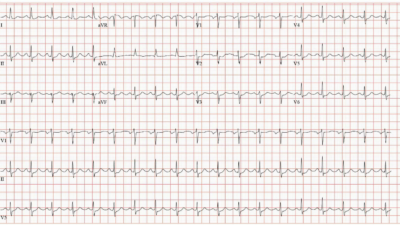

We’ve reviewed the ECG clues to acute PE in those more than 20 links that Dr. Meyers’ lists above. I found today’s initial ECG interesting — in that most of the time, the ECG diagnosis of acute PE is highlighted by more than just a couple of the ECG Findings that I list below in Figure-2.

- For example, in today’s initial ECG (that I’ve reproduced and labeled in Figure-1) — there is no sinus tachycardia — and no right axis, RAA, incomplete or complete RBBB, tall R in lead V1, persistent precordial S waves, ST elevation in lead aVR or AFib.

That said — the following are present in today’s case:

- An S1Q3T3.

- Deep symmetric T wave inversion in the anterior chest leads (BLUE arrows in Figure-1) — that occurs in association with T wave inversion suggesting RV “strain” is present not only in the anterior chest leads, but also in inferior leads III and aVF.

PEARL (as per Drs. Meyers and Smith): When there is T wave inversion in the chest leads — IF there is T wave inversion in both lead V1 and lead III ==> Think acute PE (and not ACS! ).

- By itself — the S1Q3T3 sign seen in Figure-1 would not be specific for acute PE (ie, I have seen this sign in healthy individuals with no acute pulmonary pathology). However, in the presence of a suggestive history and the extensive T wave inversion seen in today’s case — the S1Q3T3 strongly supports the diagnosis of acute PE.

- T wave inversion as diffuse as is seen in Figure-1 — most often suggests a sizeable PE (which makes it all the more surprising that there is no tachycardia and a lack of more of those ECG findings that are listed in Figure-2).

- Finally — the Q in lead III — the ST coving with slight ST elevation + T wave inversion in leads III and aVF — and the ST segment straightening in lead aVL — might lead one to misinterpret today’s ECG as indicative of ACS. IF tempted to do so — it is worth rereading the above PEARL!

Figure-1: I’ve labeled the initial ECG in today’s case.